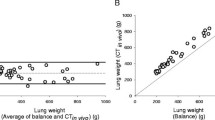

Figure 2a and b exhibit the value changes of the fractional tissue volume and the radiologic tissue volume, respectively.

(a,b) The value changes of the fractional tissue volume (a) and of the radiologic tissue volume (b). (c) The values of radiologic tissue volume of the left and right lungs in each canine at 6 months after surgery. (d,e) The value changes of the average lung density (d) and of the radiologic lung weight (e). (f) The values of radiologic lung weight of the left and right lungs in each canine at 6 months after surgery. (g) Correlation between radiologic tissue volume and radiologic lung weight. Bi: Bilobectomy, PNX: Pneumonectomy.

The change rates of fractional tissue volume, reflecting the density of lung tissue, were 98.8 ± 2.2% in the Pneumonectomy group, 106.3 ± 7.0% in the Bilobectomy group, and 98.2 ± 7.3% in the Sham group at 6 months post-surgery. The fractional tissue volume showed a change rate of 6.9% which was significantly lower than the 32.5% change rate in the lung volume (p = 0.0025, Fig. 2a).

The values of the radiologic tissue volume at 6 months post-surgery in the Sham, Bilobectomy, and Pneumonectomy groups were 97.2 ± 6.1 ml, 121.7 ± 11.7 ml, and 163.0 ± 17.4 ml, and the respective rates of increase were 2.4 ± 2.6%, 30.7 ± 7.4%, and 71.5 ± 7.4%, respectively. The rates of increase were significantly higher in the Pneumonectomy group than in the other two groups (p < 0.001, each, Fig. 2b), and the rate of increase in the Bilobectomy group was significantly higher than the one found in the Sham group. These findings are consistent with our results pertaining to the radiologic tissue volume.

Radiologic lung weight

The values of radiologic lung weight showed the same tendencies as the values of the radiologic tissue volume (Fig. 2d,e). More specifically, radiologic lung weight values at 6 months after surgery were 102.9 ± 6.5 g, 128.6 ± 11.9 g, and 172.5 ± 18.6 g in the Sham, Bilobectomy, and Pneumonectomy groups, respectively. Furthermore, the rates of increase in the postoperative 6 months were 2.0 ± 2.7%, 30.3 ± 7.2%, and 71.3 ± 7.0%, respectively. The rates of increase were significantly higher in the Pneumonectomy group compared to the other two groups (p < 0.001), and the rates of increase in the Bilobectomy group was significantly higher than the rate in the Sham group (p < 0.001). They showed the same tendencies with radiologic tissue volume. For comparison, the values of radiologic tissue volume and radiologic lung weight of the left and right lungs in each canine 6 months after surgery are presented in Fig. 2c and f.

Correlation between radiologic tissue volume and radiologic lung weight

There was a strong correlation between radiologic tissue volume and radiologic lung weight (correlation coefficient = 0.929, 95% CI 0.795–0.977, p < 0.001, Fig. 2g).

Both radiologic tissue volume and radiologic lung weight were significantly positively correlated with histologic parenchymal amounts (correlation coefficient = 0.955 and 0.934, respectively, and p < 0.001 each, Fig. 4).